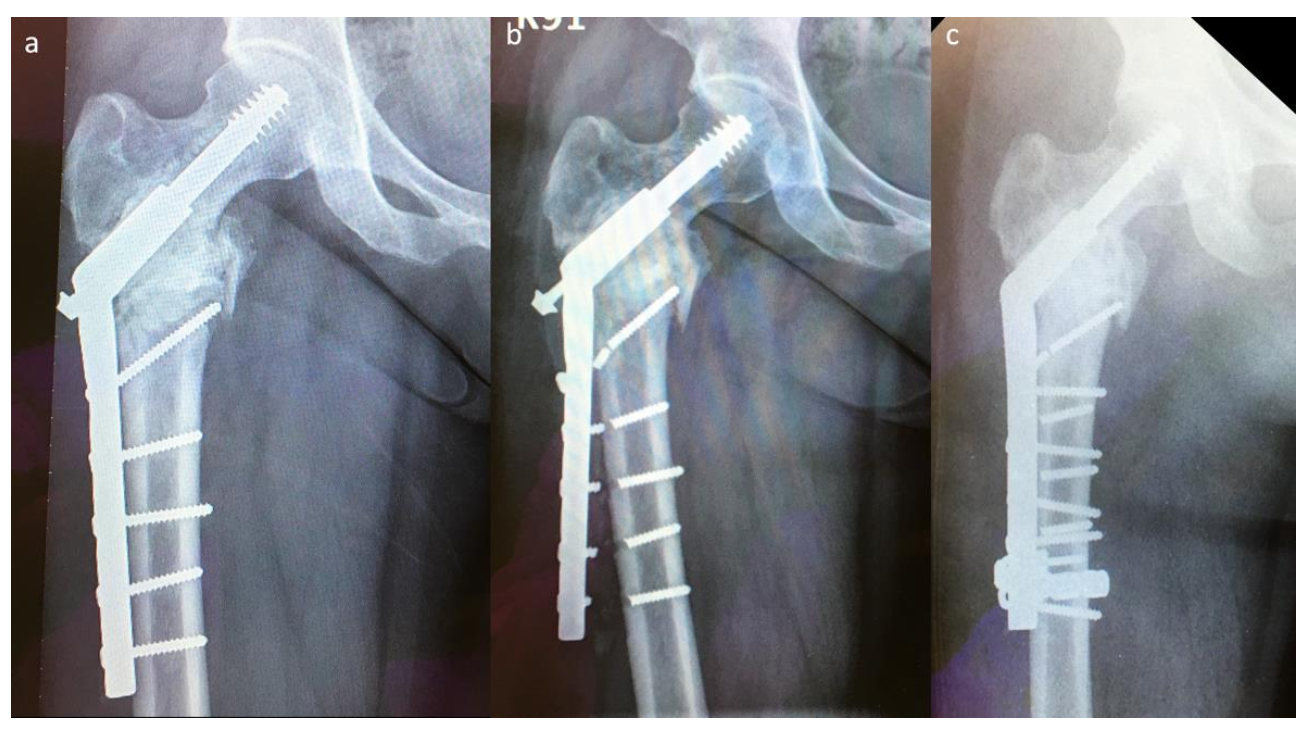

Nonetheless, there are drawbacks in using conventional SHS in the treatment of pathologically impending or actual peritrochanteric fractures. The complication rate with the SHS construct is reportedly as high as 42%, compared with that of EPR (3.1%) and IMN (6.1%); however, SHS remains the necessary choice for surgical treatment of pathologic peritrochanteric fractures [8]. Figure 1 shows a difficult case with multiple implant failures treated using conventional SHS technique complicated with cement augmentation loosening, non-union and broken screws, and all these increased difficulty in revision surgery. Longer SHS side plates are needed to provide better strength against the shearing force in each revision surgery. Therefore, in this retrospective comparative study, we compared two methods: a modified SHS technique augmented using cerclage reconstruction plates to reduce implant failure rate and to provide an alternative when performing revision ORIFs to treat patients with pathologically impending or actual peritrochanteric fractures caused by bone metastases, and conventional SHS. We also aimed to identify the factors that are associated with revision surgery.

Figure 1.

A difficult case with multiple implant failures: (a) preoperative X-ray image, (b) first-time implant failure, (c) second-time implant failure, (d) third-time implant failure, and (e) fourth-time implant failure.